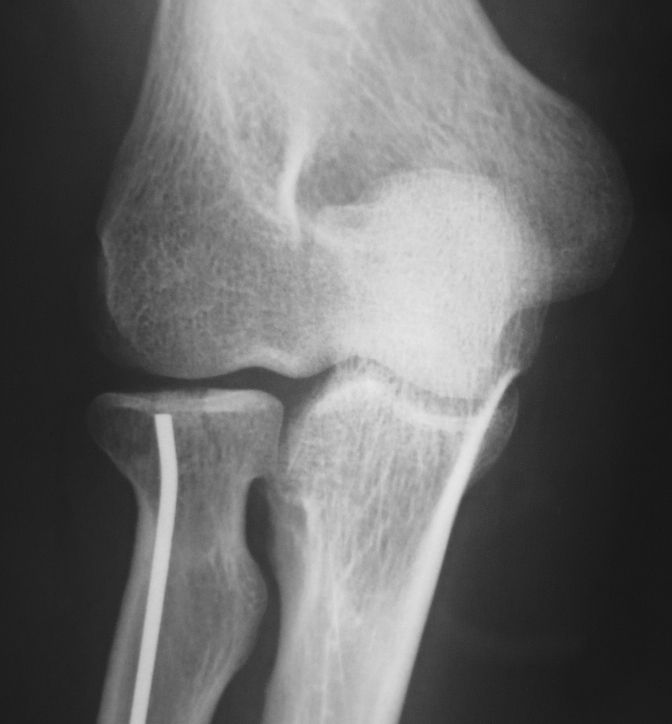

今日の午後は橈骨頭骨折の手術を行いました。単純X線像では分かりにくいのですが、CTを再構成した前額断像では関節面中央のみが陥没しているタイプの骨折でした。

比較的橈骨頚部の連続性は保たれていたので、橈骨頚部骨折と同様のK-wireを用いた整復・固定術を施行しました。今回使用したK-wireは2.0mmです。

まず、橈骨茎状突起先端の直上に約1cmの切開を加えて皮下を鈍的に剥離して橈骨茎状突起部を展開しました。橈骨神経浅枝損傷を避けるためにエアターニケットを使用します。

2.0 K-wireで皮質骨を開窓してから一旦抜去します。K-wireのお尻側の先が鈍な方を先頭にして、再度橈骨内に刺入します。この時にK-wireの先端を僅かに曲げておきます。

ハンマーで叩打しながら橈骨内を中枢方向に進めていきます。橈骨骨幹部を過ぎると急に抵抗が無くなり、あっという間に橈骨頚部に到達するので叩き過ぎに注意します。

橈骨頚部に到達した時点で、先ほど曲げたK-wire先端の方向を微調整します。橈骨茎状突起部のK-wireの断端は皮下に埋没しました。橈骨神経浅枝に接触しないように位置を調整します。

今日の手術も10分程度で終了しました。低侵襲なのに得られるメリットが大きいので良い手術だと思います。